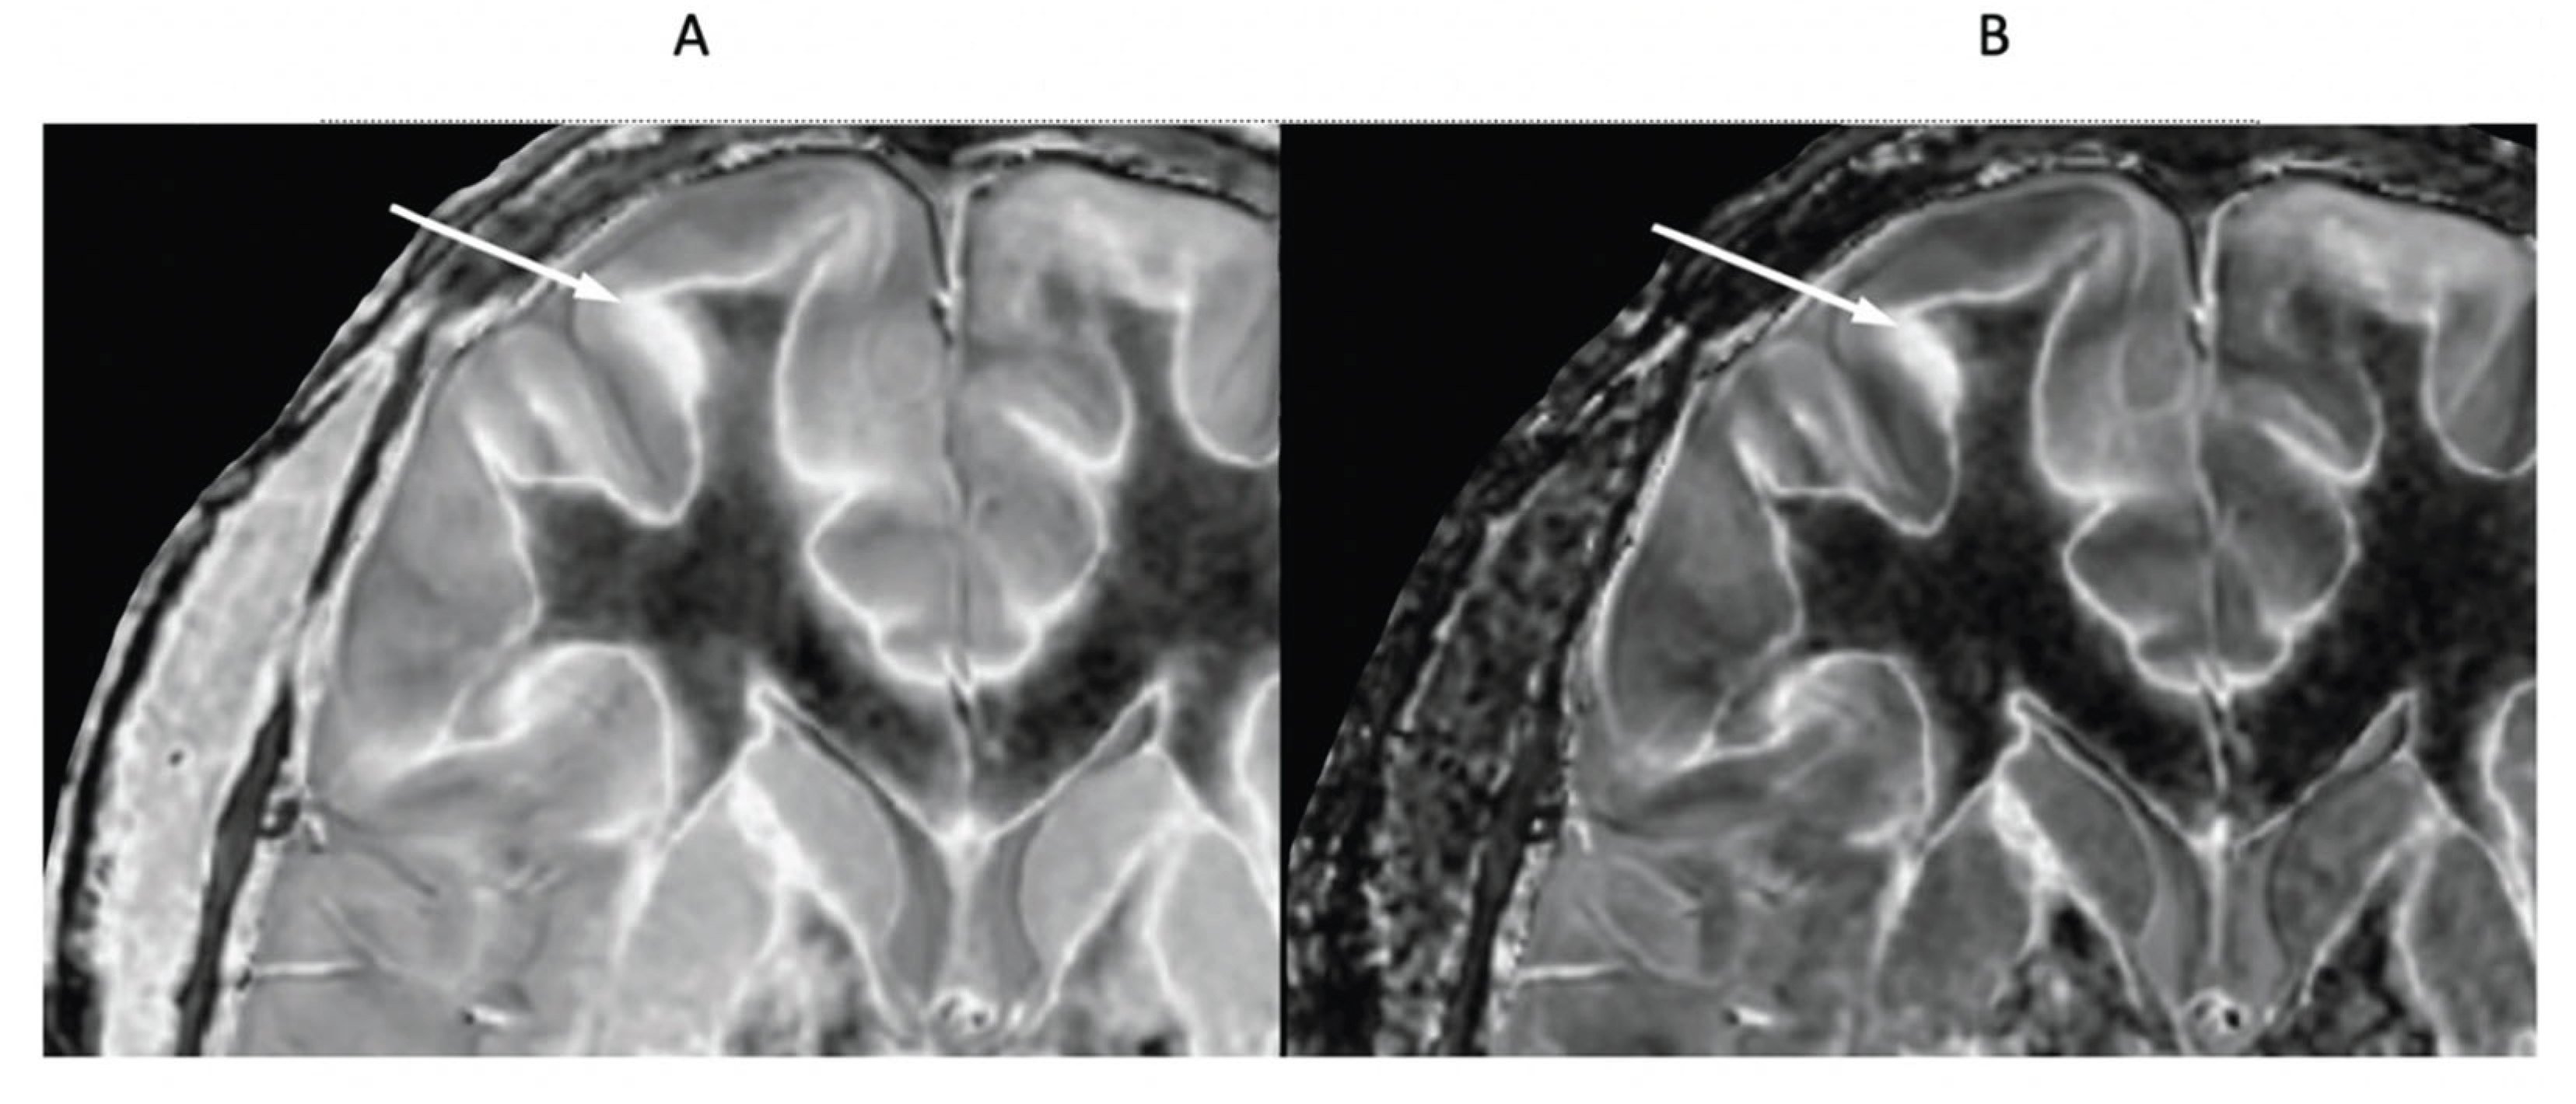

- Mild Traumatic Brain Injury (mTBI)

- Multiple Sclerosis (MS)

- Normal Control and MS Patient with dSIR and lSIR Images

- Newburn, G.; McGeown, J.P.; Kwon, E.; Tayebi, M.; Condron, P.; Emsden, T.; Holdsworth, S.J.; Cornfeld, D.M.; Bydder, G.M. Targeted MRI (tMRI) of Small Increases in the T1 of Normal Appearing White Matter in Mild Traumatic Brain Injury (mTBI) Using a Divided Subtracted Inversion Recovery (dSIR) Sequence. OBM Neurobiol. 2023, 07, 1–27. [Google Scholar] [CrossRef]